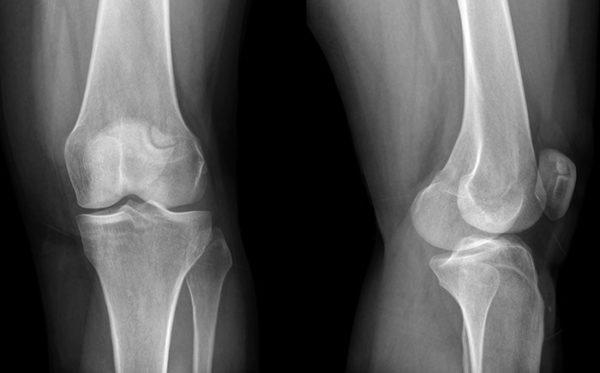

Общие симптомы заболеваний колена

При любых заболеваниях коленных суставов наблюдаются схожие симптомы. К ним относятся болевые ощущения в области колена, щелчки, ограничение подвижности, усиление дискомфорта при ходьбе и сгибании, отечность, припухлость тканей, а в некоторых случаях — деформация сустава и покраснение кожи.

Артроз

Это разрушение хрящевой ткани в коленном суставе и образование остеофитов, то есть костных наростов. Артроз приводит к деформации, сужению суставной щели и образованию анкилоза. Постепенно, если не проводить лечение, щель между суставами полностью исчезает, и подвижность сустава теряется.